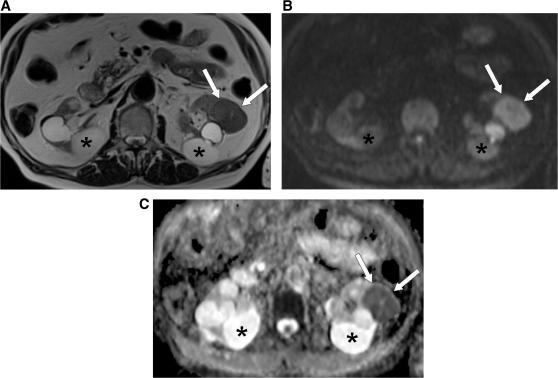

Diffusion-weighted magnetic resonance imaging (DW-MRI) appears to hold promise as a non-invasive imaging modality in the detection of early microstructural and functional changes of different organs. DW-MRI is an imaging technique with a high sensitivity for the detection of a large variety of diseases in the urogenital tract. In kidneys, DW-MRI has shown promise for the characterization of solid lesions. Also in focal T1 hyperintense lesions DW-MRI was able to differentiate hemorrhagic cysts from tumours according to the lower apparent diffusion coefficient (ADC) values reported for renal cell carcinomas. Promising results were also published for the detection of prostate cancer. DW-MRI applied in addition to conventional T2-weighted imaging has been found to improve tumour detection. On a 3 T magnetic resonance unit ADC values were reported to be lower for tumours compared with the normal-appearing peripheral zone. The combined approach of T2-weighted imaging and DW-MRI also showed promising results for the detection of recurrent tumour in patients after radiation therapy. DW-MRI may improve the performance of conventional T2-weighted and contrast-enhanced MRI in the preoperative work-up of bladder cancer, as it may help in distinguishing superficial from muscle invasive bladder cancer, which is critical for patient management. Another challenging application of DW-MRI in the urogenital tract is the detection of pelvic lymph node metastases. As the ADC is generally reduced in malignant tumours and increased under inflammatory conditions, reduced ADC values were expected in patients with lymph node metastases.

弥散加权磁共振成像(DW-MRI)似乎有望成为一种非侵入性的成像方式,用于检测不同器官的早期微观结构和功能变化。DW-MRI 是一种对泌尿生殖系统多种疾病具有高灵敏度的成像技术。在肾脏中,DW-MRI 已显示出对实体病变进行特征描述的潜力。在局灶性 T1 高信号病变中,DW-MRI 也能够根据报告的肾细胞癌较低的表观扩散系数(ADC)值,将出血性囊肿与肿瘤区分开来。在前列腺癌的检测中也取得了有前途的结果。DW-MRI 与常规 T2 加权成像联合应用已被发现可提高肿瘤检测的灵敏度。在 3T 磁共振仪上,与正常外观的外周带相比,肿瘤的 ADC 值较低。T2 加权成像和 DW-MRI 的联合应用也显示出在放射治疗后检测复发性肿瘤方面有很好的效果。DW-MRI 可能会改善常规 T2 加权和对比增强 MRI 在膀胱癌术前评估中的性能,因为它可能有助于区分表浅性和肌层浸润性膀胱癌,这对患者管理至关重要。DW-MRI 在泌尿生殖系统中的另一个具有挑战性的应用是检测盆腔淋巴结转移。由于 ADC 通常在恶性肿瘤中降低,而在炎症条件下升高,因此预计淋巴结转移患者的 ADC 值会降低。